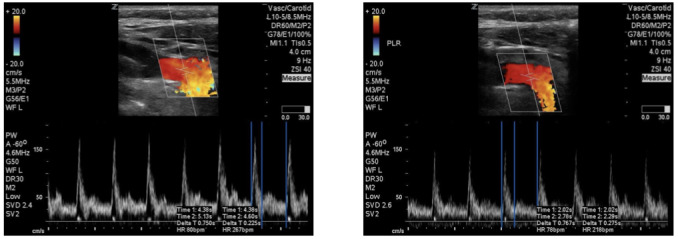

目标:很难确定哪些患者的心输出量会因容量管理而增加。我们建议使用颈动脉血流时间,这是确定患者是否对容量有反应的一种非侵入性方法。方法我们选取了入住重症监护病房并安装了肺动脉导管的患者。我们对被动抬腿前后的心输出量进行颈动脉流速时间和肺动脉导管测量,并将两者进行比较。被动抬腿前与被动抬腿后的测量值若增加 10%,则表明患者对容量有反应。结果:通过金标准肺动脉导管的测定,我们确定了 8 名患者有容量反应。敏感性为 87.5%,特异性为 90.9%。PA-CO 测量值与 CFT 之间的皮尔逊相关系数为 r=0.8316,表明这两种测量值之间具有很强的相关性。结论在使用肺动脉导管的重症患者样本中,我们发现颈动脉血流校正时间与肺动脉导管的心输出量测量值之间存在很强的相关性。

Objectives: Identifying patients who will have an increase in their cardiac output from volume administration is difficult to identify. We propose the use of carotid flow time, which is a non-invasive means to determine if a patient is volume responsive. Methods: Patients admitted to a critical care unit with a pulmonary artery catheter in place were enrolled. We perform a carotid flow time and pulmonary artery catheter measurement of cardiac output pre and post-passive leg raise and comparing the two. An increase of 10% change in the pre- vs. post-passive leg raise measurement would be indicative of a patient who is volume responsive. Results: We identified 8 patients who were volume responsive as determined by the gold standard pulmonary artery catheter. The sensitivity 87.5% and specificity 90.9%. Pearson correlation coefficient between PA-CO measurements and CFT was r=0.8316, indicative of strong correlation between the two measurements. Conclusion: In our patient sample of critically ill patients with pulmonary artery catheters, we found a strong correlation between corrected carotid flow times and cardiac output measurements from pulmonary artery catheters.